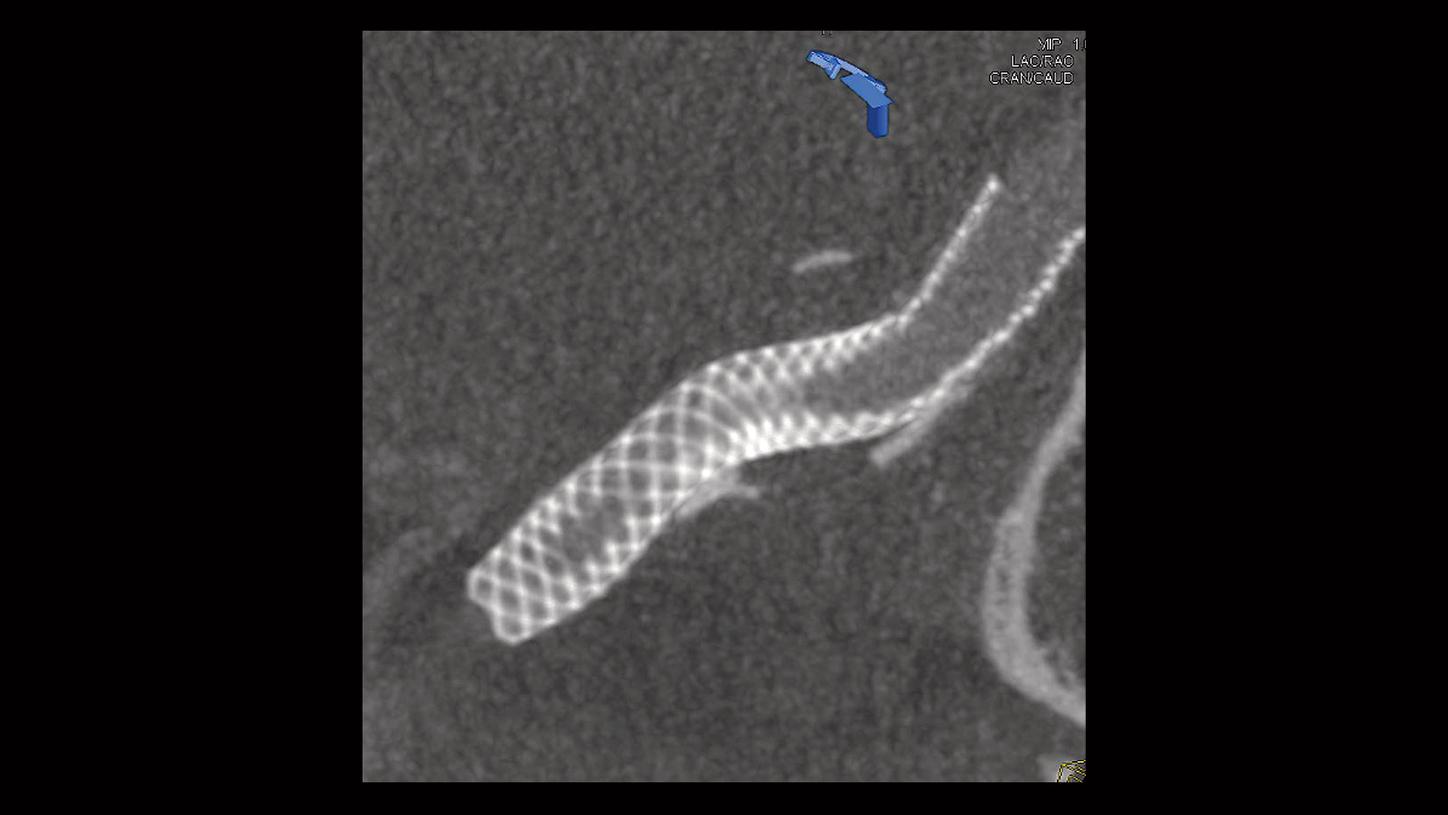

Artis Q is visionary in performance - with its high performance, advanced 3D imaging, and excellent contrast resolution at virtually any angle and for challenging patient sizes In fact, the spatial resolution that can be achieved in 3D images is 3.5 lp/mm, resolving objects as small as 140 µm Artis Q offers unparalleled performance with the new powerful GIGALIX X-ray tube for high contrast resolution at any angle and any patient size, while the optimized X-ray pulse helps to reduce radiation by up to 60%

Ангиограф Artis Q Сименс купить в Москве, цена на Artis Q Stormoff. Artis Q.zen inaugurates a groundbreaking new detector technology based In fact, the spatial resolution that can be achieved in 3D images is 3.5 lp/mm, resolving objects as small as 140 µm